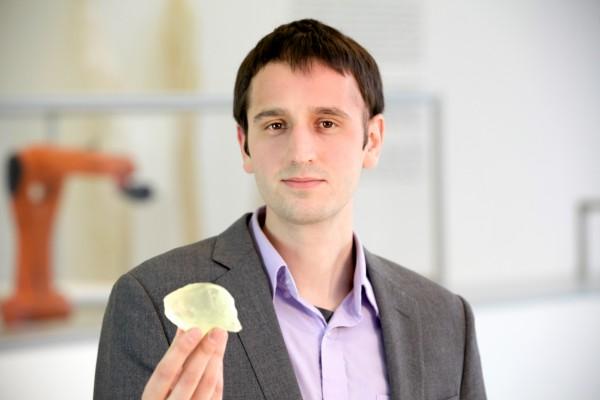

An MIT graduate student’s research into 3-D printing helped doctors remove a tumor from his brain last August, and he is now sharing his story as an advocate for increased patient access to their own medical records.